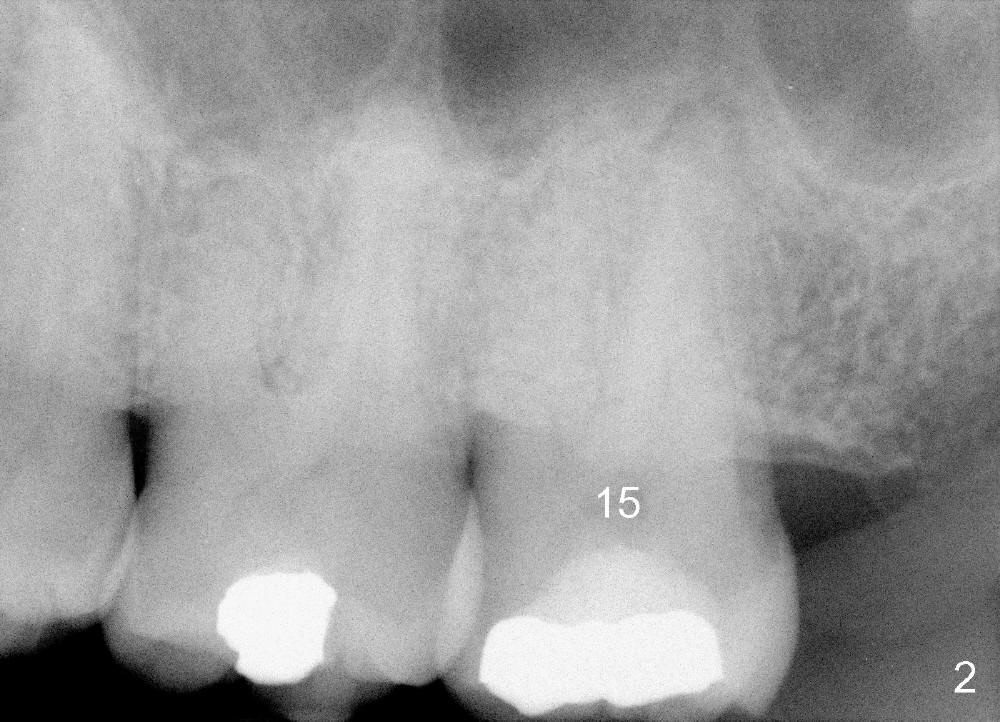

A 52-year-old black man fails to return to finish root canal therapy for the tooth #15; ultimately it is non-salvageable (Fig.1-3).  The tooth has 3 basically fused roots (Fig.4 black (buccal) and red (palatal) outlines), above which is the sinus septum (*).  By inserting an immediate implant into the sinus septum, primary stability should be high (Fig.5 vs. 6).